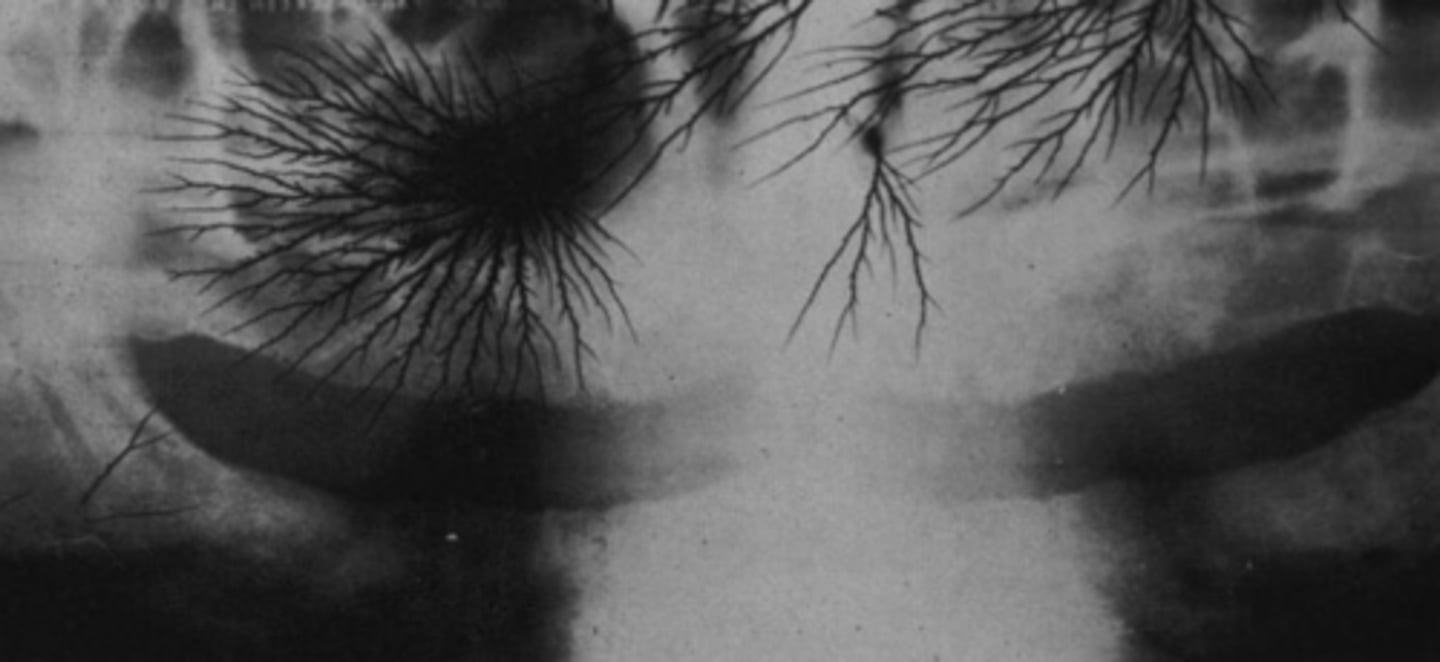

What is produced from the film handling errors static electricity pattern?

Static charge produces lighting bolt patterns

What error occurred here?

Static electricity